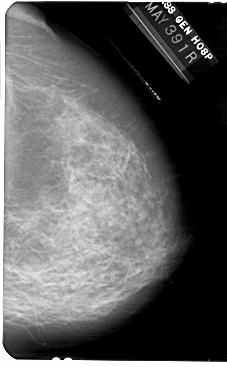

A_1733_1.RIGHT_MLO

RIGHT_MLO LINES 5491 PIXELS_PER_LINE 3796 BITS_PER_PIXEL 12 RESOLUTION 43.5 NON_OVERLAY